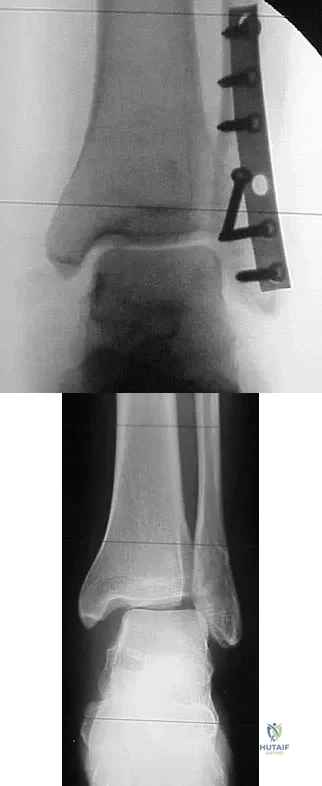

Question 49

A 75-year-old woman began a walking program 2 months after undergoing right total knee arthroplasty. She had to stop the program after 4 weeks because of hindfoot pain and ankle swelling. Radiographs are shown in Figures 42a and 42b. What is the most likely diagnosis?

Explanation